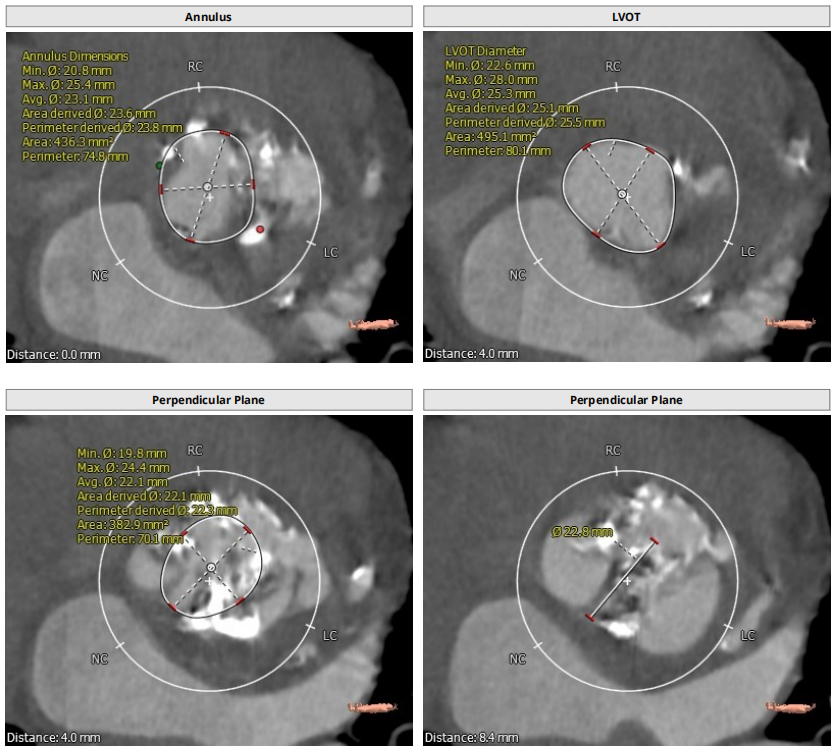

根部解剖

患者为TYPE0二叶瓣,重度钙化,术前可见瓣周突出物,怀疑囊肿,瓣环23.8,LVOT25.5,鱼嘴开口22.8,预计瓣口开口22.3,STJ33.9,窦部空间大,左右冠高度分别为19.9和21.5,预计18号球囊预扩。